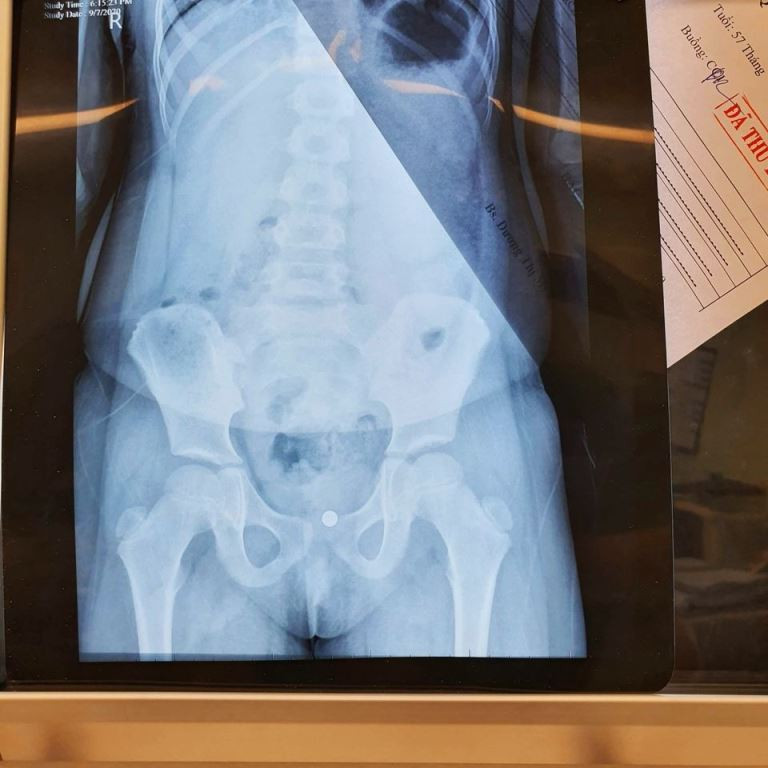

Hình ảnh viên bi trong âm đạo (ảnh: BVCC) Tại đây sau chụp chiếu các phim xác định vị trí, các bác sĩ đã nội soi gây mê gắp dị vật trong âm đạo cho bé gái. Trường hợp này để lâu sẽ bị viêm nhiễm lâu ngày, nếu lâu hơn nữa có thể gây thủng vách giữa bàng quang và âm đạo, xuất huyết và phẫu thuật cho những trường hợp đã biến chứng là cực kỳ phức tạp.